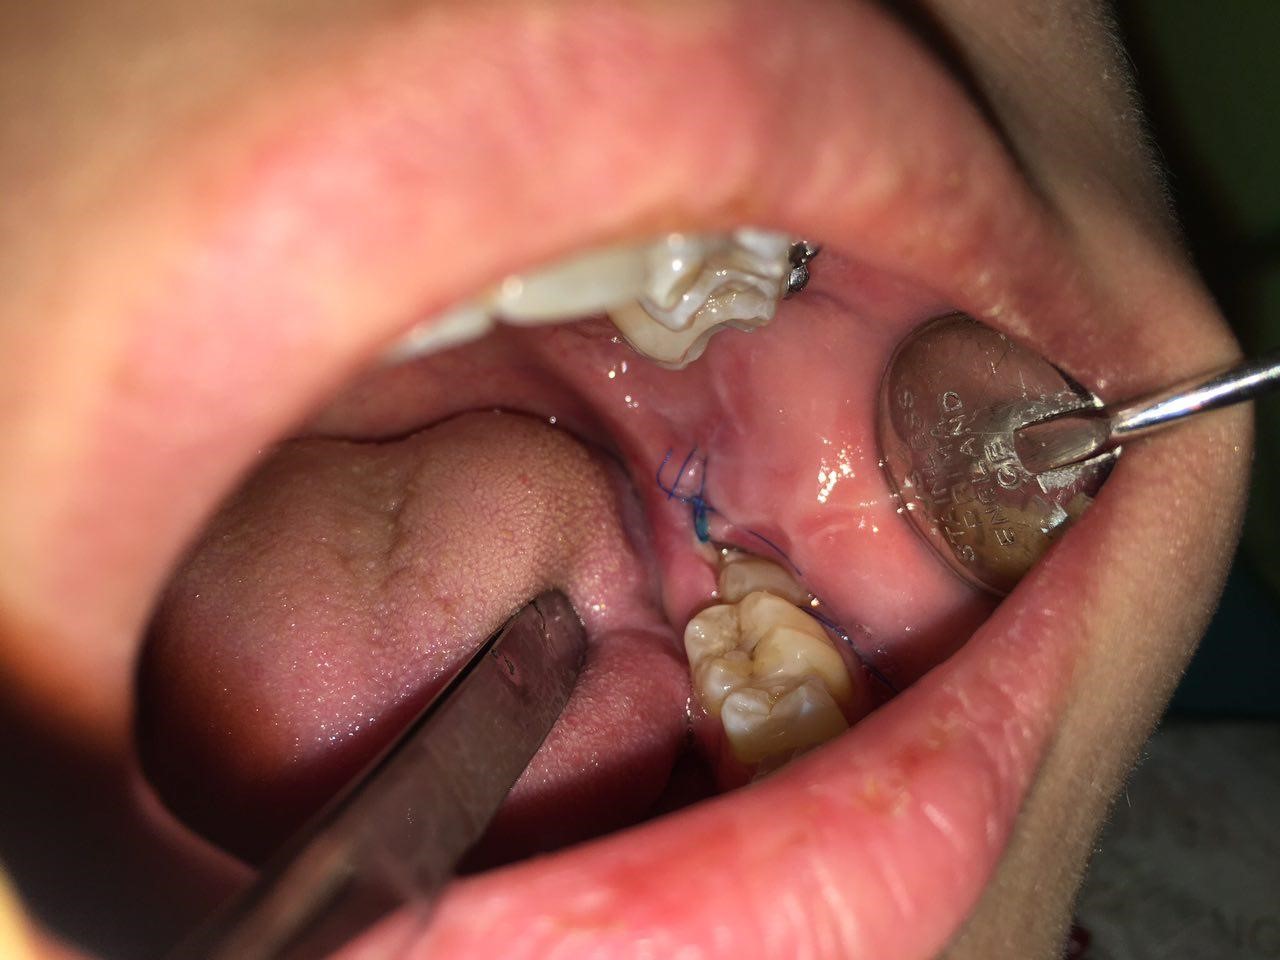

Методи діагностики та лікування запалених ясен біля вісімки

Визначити, чому опухли ясна біля зуба мудрості, допомагають різні діагностичні маніпуляції. Вони включають огляд ротової порожнини в лікаря та дослідження за показаннями. Стоматолог може обстежити ясна з мікроскопом, призначити рентген зуба чи всієї щелепи, виміряти глибину пародонтальних кишень тощо. За результатами діагностики стоматолог приймає рішення про медикаментозне лікування, терапевтичні маніпуляції чи видалення проблемного зуба.

На початковій стадії перикороніту добре допомагають протизапальні засоби. Запалені ясна обробляються мазями для зняття больових відчуттів. Покращенню загального стану сприяють анальгетики. За призначенням лікаря використовуються полоскання ротової порожнини антисептичними розчинами. За наявності гнійного ексудату треба проводити маніпуляції з видалення уражених тканин. Якщо зуби ростуть неправильно чи мають патологічну анатомію, зберігати їх немає сенсу.

Коли потрібне висічення капюшона зуба мудрості?

Щоб полегшити прорізування вісімки та покращити стан пацієнта, стоматолог може прийняти рішення про видалення капюшона.